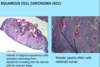

A: Name the 2nd most common Skin Tumor

B: Risk Factors (11)

C: What’s the BIGGEST Risk Factor and why

A: Squamous Cell Carcinoma

B: HAIR IN WOMBS

- [HRAS activating mutation]

- Arsenic

- Immunosuppresion (HPV)

- Radiation-ionizing

- Industrial

- [Notch receptor LOSS OF FUNCTION mutation]

- Wounds-chronic

- Older

- Males

- Burn Scars

- SUN!!!!! = BIGGEST RISK FACTOR!

C: Sun–>[TP53 mutation at pyrimidine dimers] (INC potential in Xeroderma Pigmentosum pts)

A: Describe Histology (3)

B: Dz

A: image

B: [Squamous Cell Carcinoma]

A: Describe Histology in each image

B: Dz

A: image

B: [Squamous Cell Carcinoma]